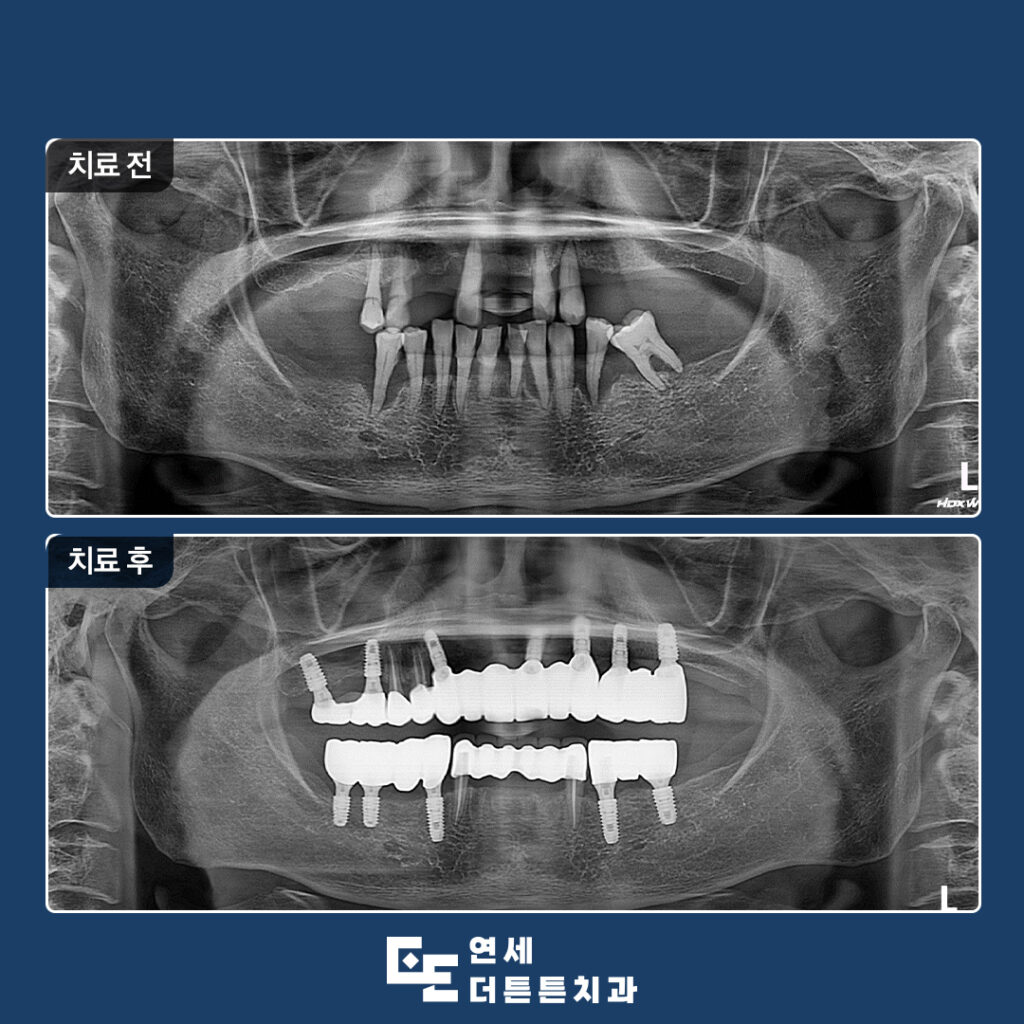

방학역치과 연세더튼튼치과에서 소개해 드릴 사례는

예후가 좋지 않은 자연치들을 발치한 이후

임플란트를 통해 구강 기능을 회복한 치료 과정입니다.

잇몸이 안 좋아서 흔들리는 치아가 많아요.

방학역치과에 내원하신 환자분께서는

여러 개의 치아가 이미 상실된 상태였고,

잇몸 염증이 장기간 진행되면서

잇몸뼈가 상당 부분 흡수되어

남아 있는 치아들 역시 흔들림이

나타나고 있는 상황이었습니다.

정밀 검사를 통해 보존이 어려운 치아는 발치를 결정하고

해당 부위에는 임플란트 치료를 계획하였으며,

기능적으로 유지가 가능한 치아는 신경치료 후

크라운 보철로 회복하는 방향으로 치료 계획을 세웠습니다.